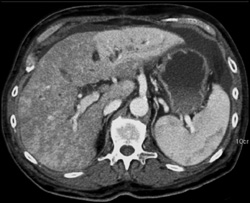

Diagnosis

Hemangioma